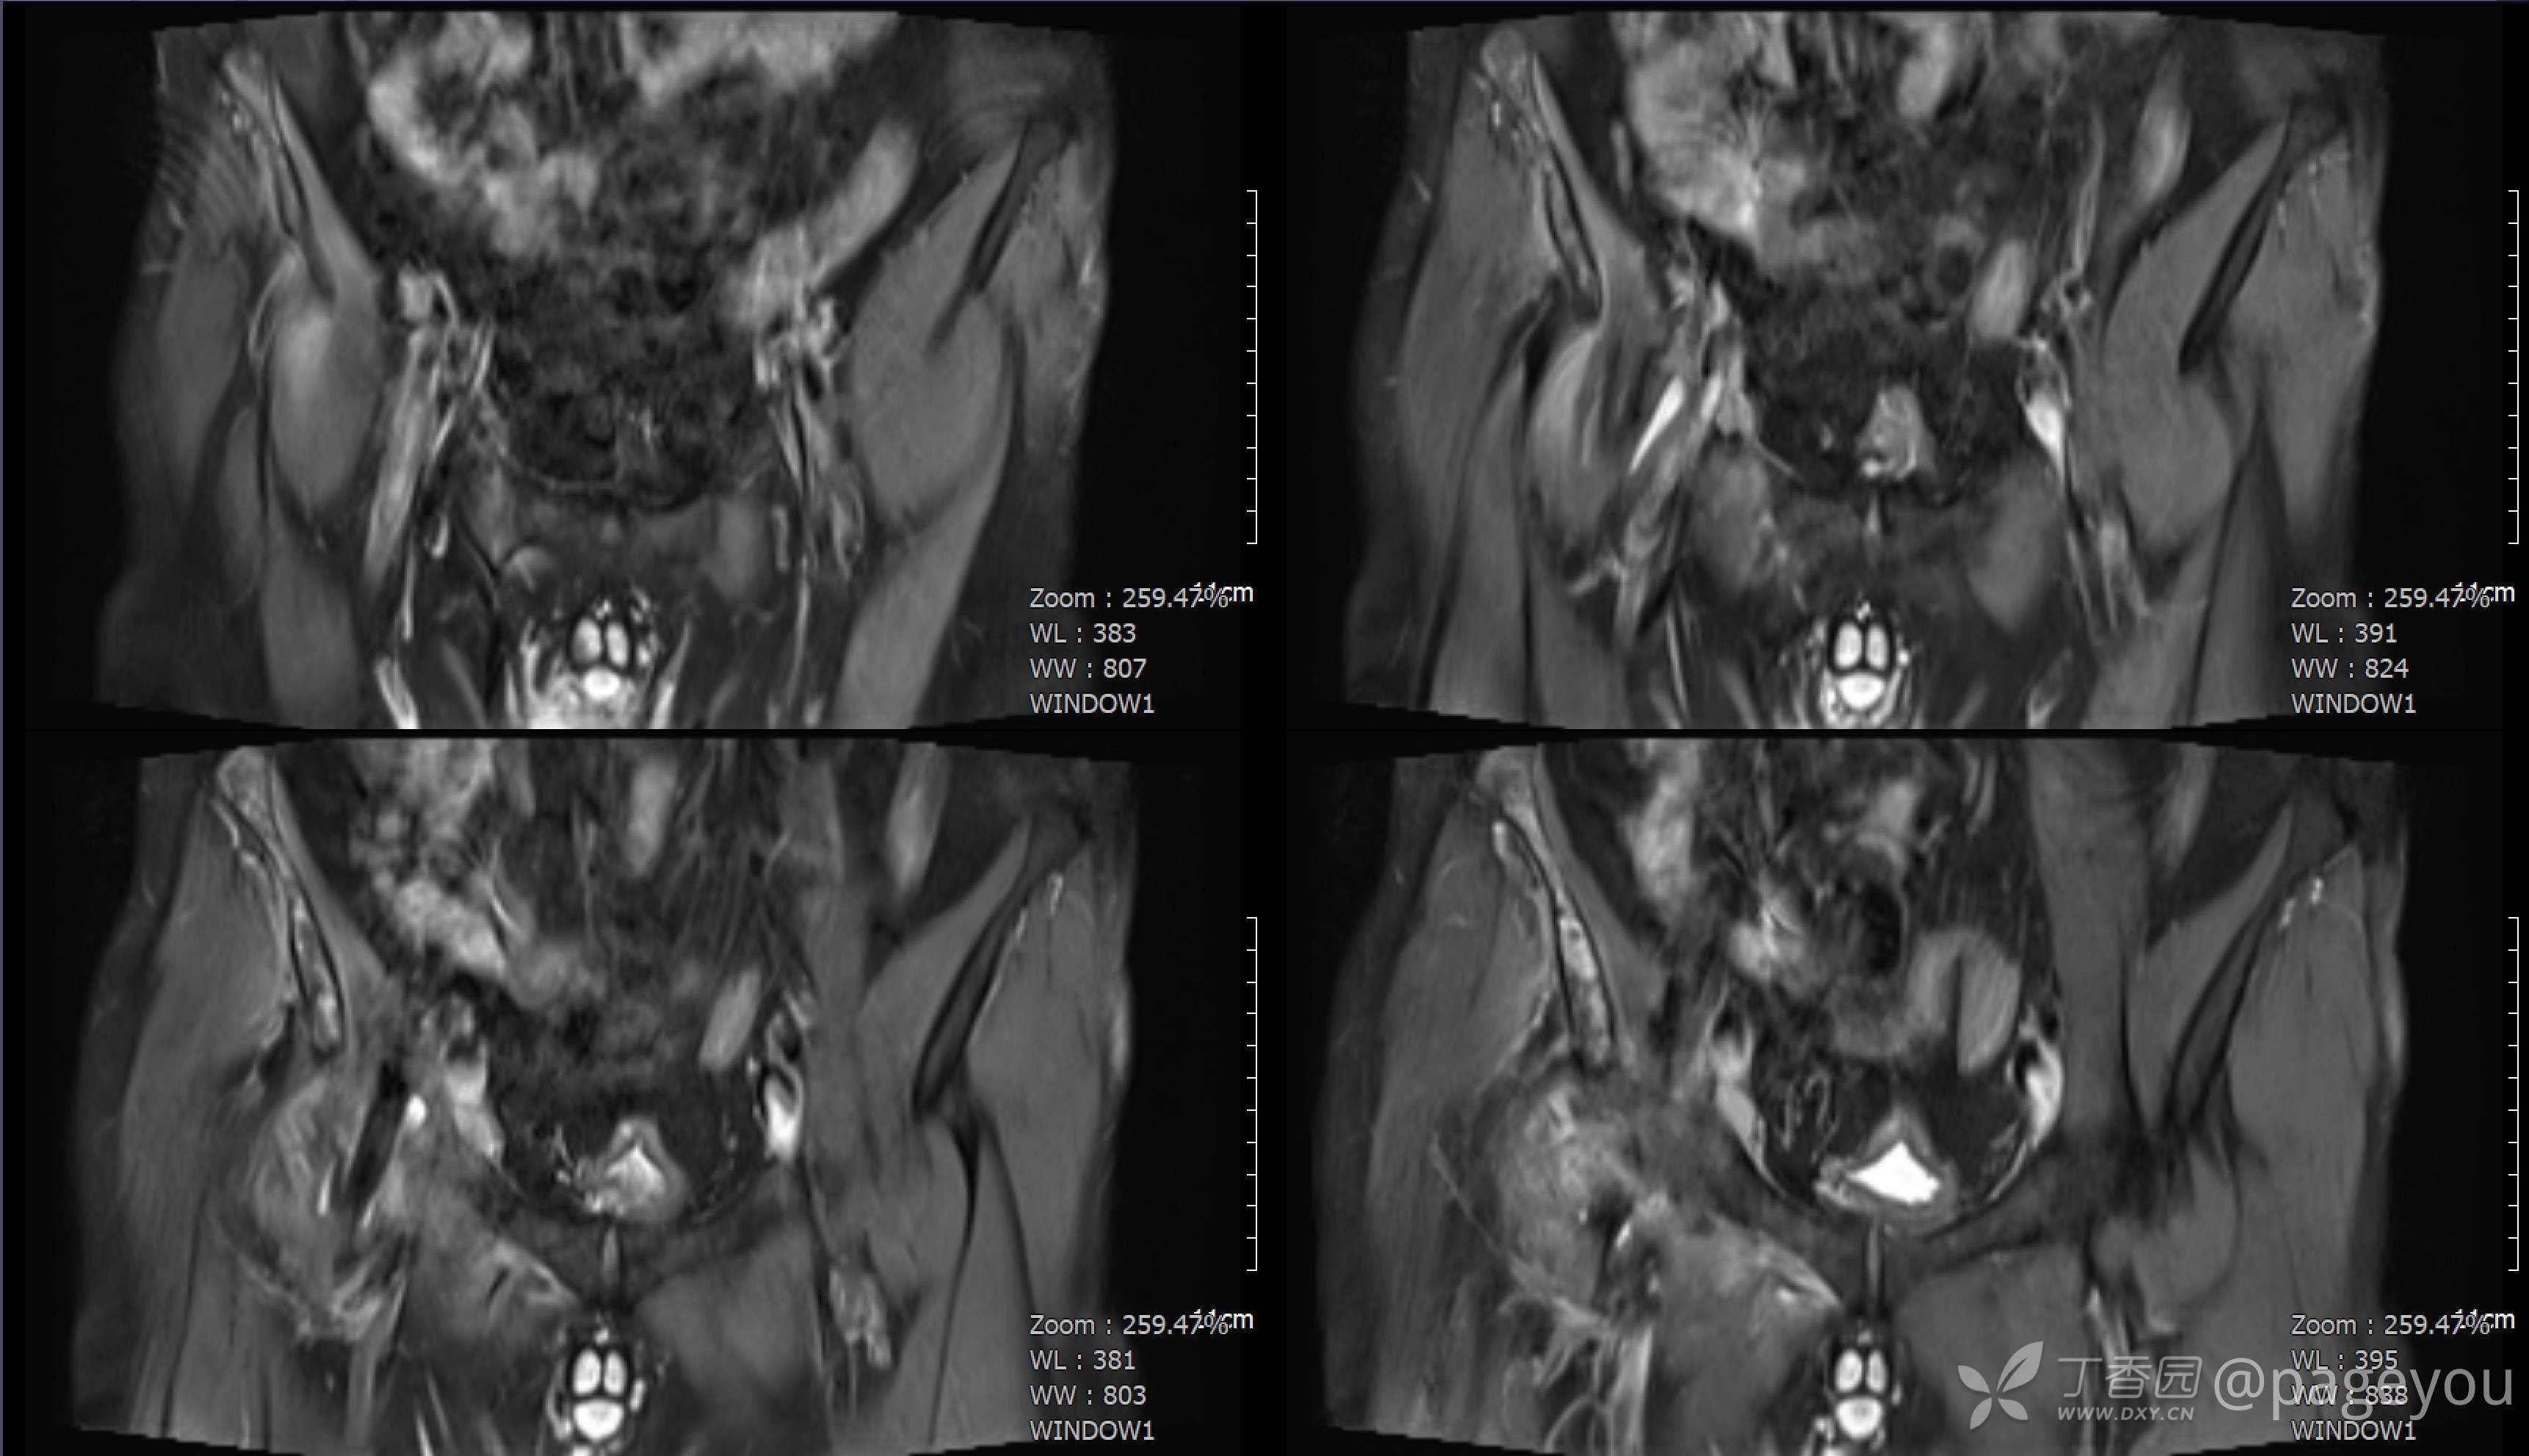

入院查腰椎MRI: